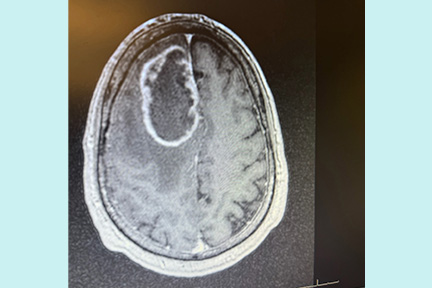

At Memorial Regional Hospital, imaging revealed the cause, a benign brain tumor. Scott describes that moment as surreal. He was confused, exhausted, and unsure what would come next.

Scott’s care team at Memorial Neuroscience Institute moved quickly. His neurosurgeon, Simon Buttrick, MD, explained the diagnosis and treatment plan with clarity and compassion. Scott also met specialists from Memorial Cancer Institute, including medical oncologists Atif Hussein, MD, and radiation oncologist Christine Feng, MD.